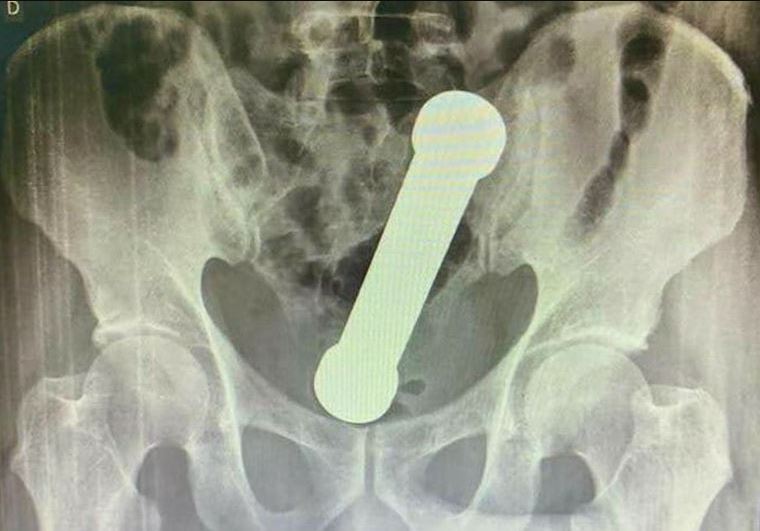

When medics at the hospital in Manaus, Brazil, were unable to remove the object using tweezers, they opted for a "manual extraction".

This meant they put their hand into the man's bum to remove the dumbbell.

According to a report in the International Journal of Surgery Case Reports written by Dr Ana Elisa de Landa Moraes Teixeira Grossi and her team, a surgeon inserted their hand "up to the forearm" to get a grip on the item.

Dr Ana wrote: "Despite the location of the object being considered high, manual transanal extraction was chosen, inserting the surgeon's forearm with some difficulty, without post-extraction complications."